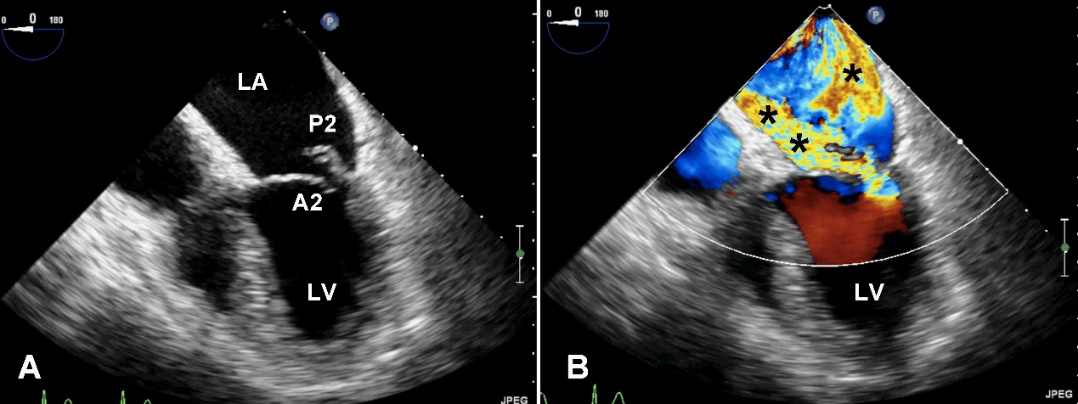

TEE切面与二尖瓣分区的对应关系可用于二尖瓣脱垂部位的判断,但要注意的是:一定要将2D或3D图像与二尖瓣模型对应起来,不理解切面和模型之间的空间关系,直接用文献上的分区对应实际的超声图像会导致定位不准和交流障碍(图11,12,13,14);另外,经胃底基底段短轴切面对诊断瓣叶裂和穿孔很有帮助,彩色多普勒可以提供有关反流束起源的信息(图14)。

图11四腔心切面显示二尖瓣后叶P2区脱垂

图14经胃底基底段短轴切面。示二尖瓣前后叶,P3区位于“扇形”的顶点

图21缩流颈的测量食管中段四腔心切面,反流束基底部宽度与二尖瓣反流的严重程度相关。

反流束的方向也很重要,其不仅仅是病因学的线索,也是严重程度的一个征象。中心性反流可由瓣环扩张或心室功能不全引起,偏心性反流(图22)常常由二尖瓣结构本身异常引起的,偏心性的贴壁反流束应该认为是中度以上的。

图22偏心性二尖瓣反流。中食管四腔心切面二尖瓣彩色多普勒血流成像,可见重度MR沿左房内侧壁走行达房顶部。